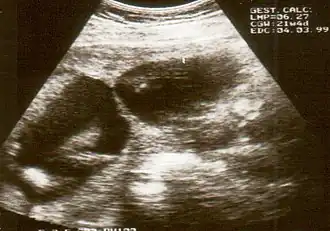

![]() Визуализация перетяжки при ультразвуковом обследовании | |

Амниотические перетяжки не всегда обнаруживаются при УЗИ, так как они очень тонкие. Иногда их наличие устанавливают косвенно по набухшим/увеличенным из-за вдавлений конечностям. Распространена и гипердиагностика. Поэтому, если появляется предположение, что обнаружены амниотические тяжи, показаны дальнейшие исследования (3D УЗИ, МРТ, эхокардиограмма эмбриона) для определения серьезности ситуации.

Обнаруженные на УЗИ во время беременности амниотические тяжи часто не приводят ни к каким негативным последствиям или порокам развития[4][5]. Около 70 % амниотических тяжей обнаруженных во время УЗИ не обнаруживаются на следующем сканировании из-за их разрыва или сдавливания[6].